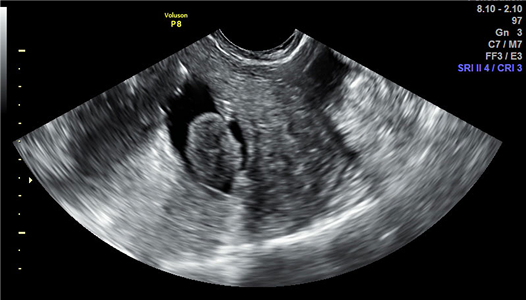

La ecografía transvaginal (2D, 3D, sonohisterografía, histerosalpingosonografía) es uno de los primeros estudios que realiza el especialista en fertilidad para evaluar el útero, los ovarios y las trompas. Además, durante los tratamientos como la Fertilización In Vitro (FIV), se realizan varias ecografías de seguimiento para:

Monitorear la evolución de los folículos durante la estimulación ovárica con la ayuda de la inteligencia artificial (Folliscan).

Verificar el grosor y desarrollo del endometrio antes de la transferencia embrionaria.